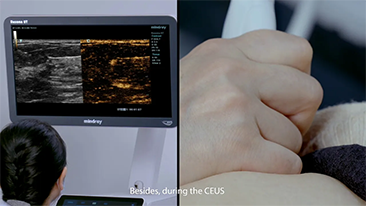

Mindray Resona General Imaging solutions help clinicians realize more accurate and efficient diagnosis and treatment results through comprehensive subdivision application probes and efficient clinical application tools.

General Imaging Products